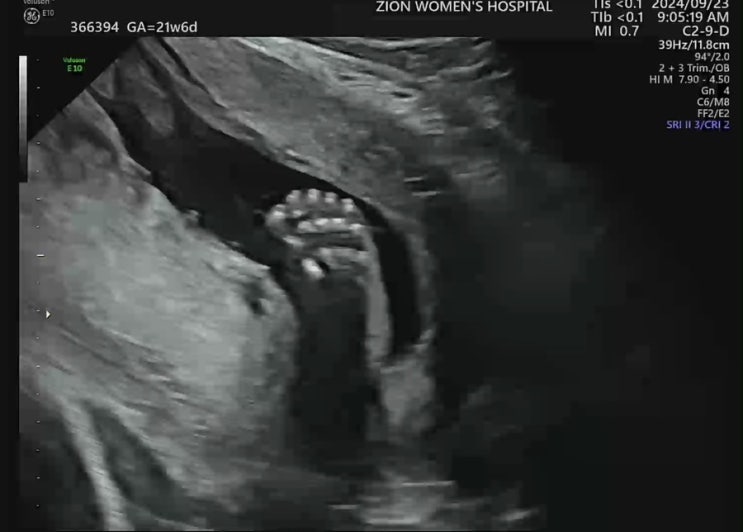

임신 17w~21w 기록 / 임신 중기 배크기 및 증상 / 정밀초음파

?17w ~ 21w 증상 기록 - 배가 나오기 시작한다 훅훅! - 18주부터 가스찬 것 같은 느낌으로 뽀글뽀글..(?...